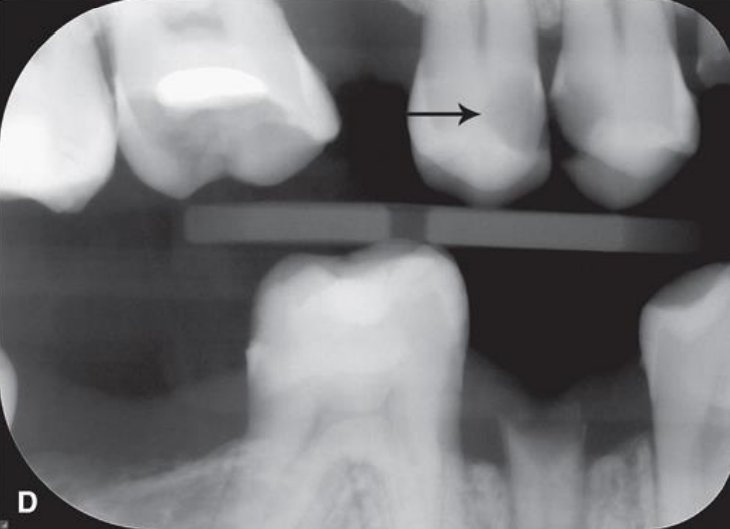

classify this lesion according to the ADA and ICDAS/ICCMS systems

caries within the outer half of the enamel: RA1, E1

classify this lesion according to the ADA and ICDAS/ICCMS systems

caries within the inner half of the enamel: RA1, E1

top arrow, classify this lesion based on the ADA caries classification system

D1